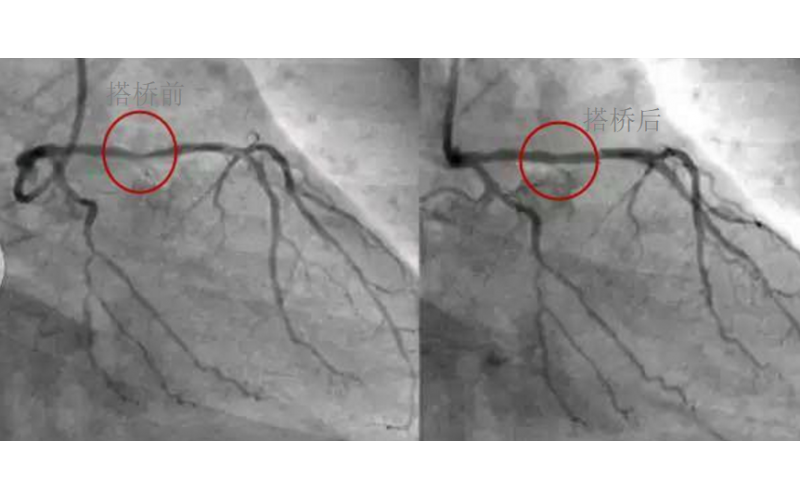

深圳市广发体育网页厂对心脏支架的关注,国产化的道路有多长?